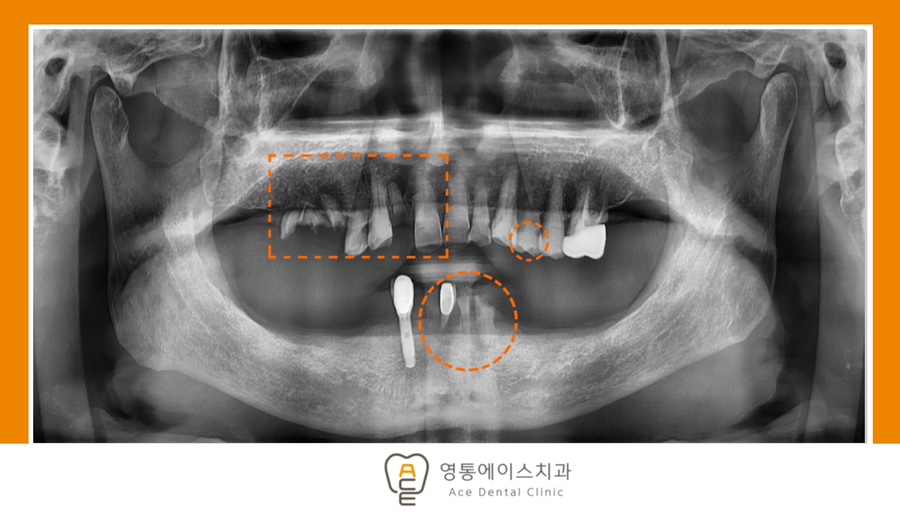

치료 전 사진 / 2025.08.27

치료 전,후 사진/2025.08.27 ~ 2026.03.09

*치료 기간 : 2025.08.27 ~ 2026.03.09